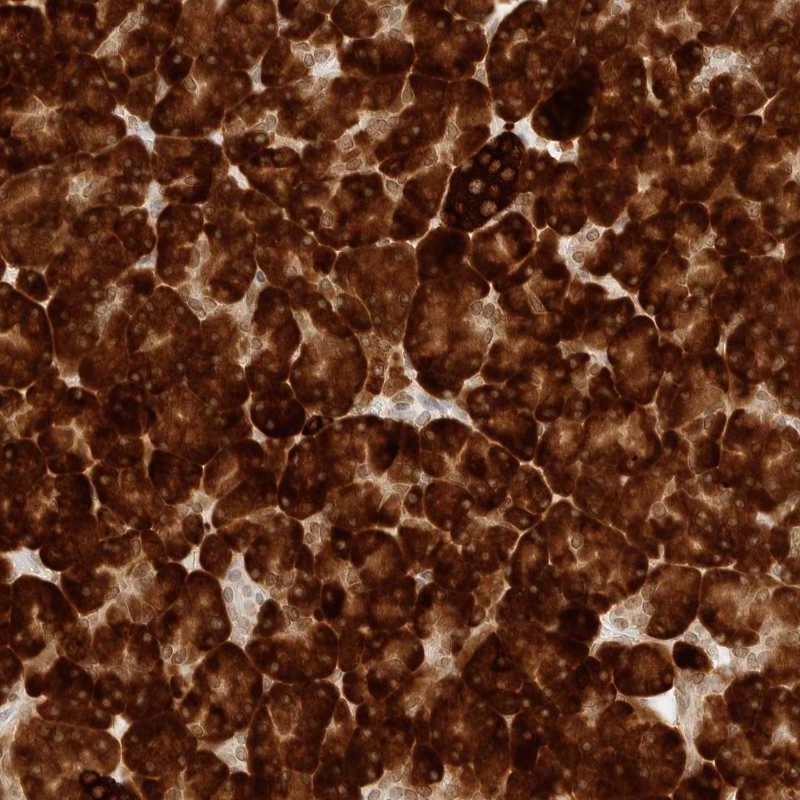

Immunohistochemical staining of human pancreas shows strong cytoplasmic positivity in exocrine cells.